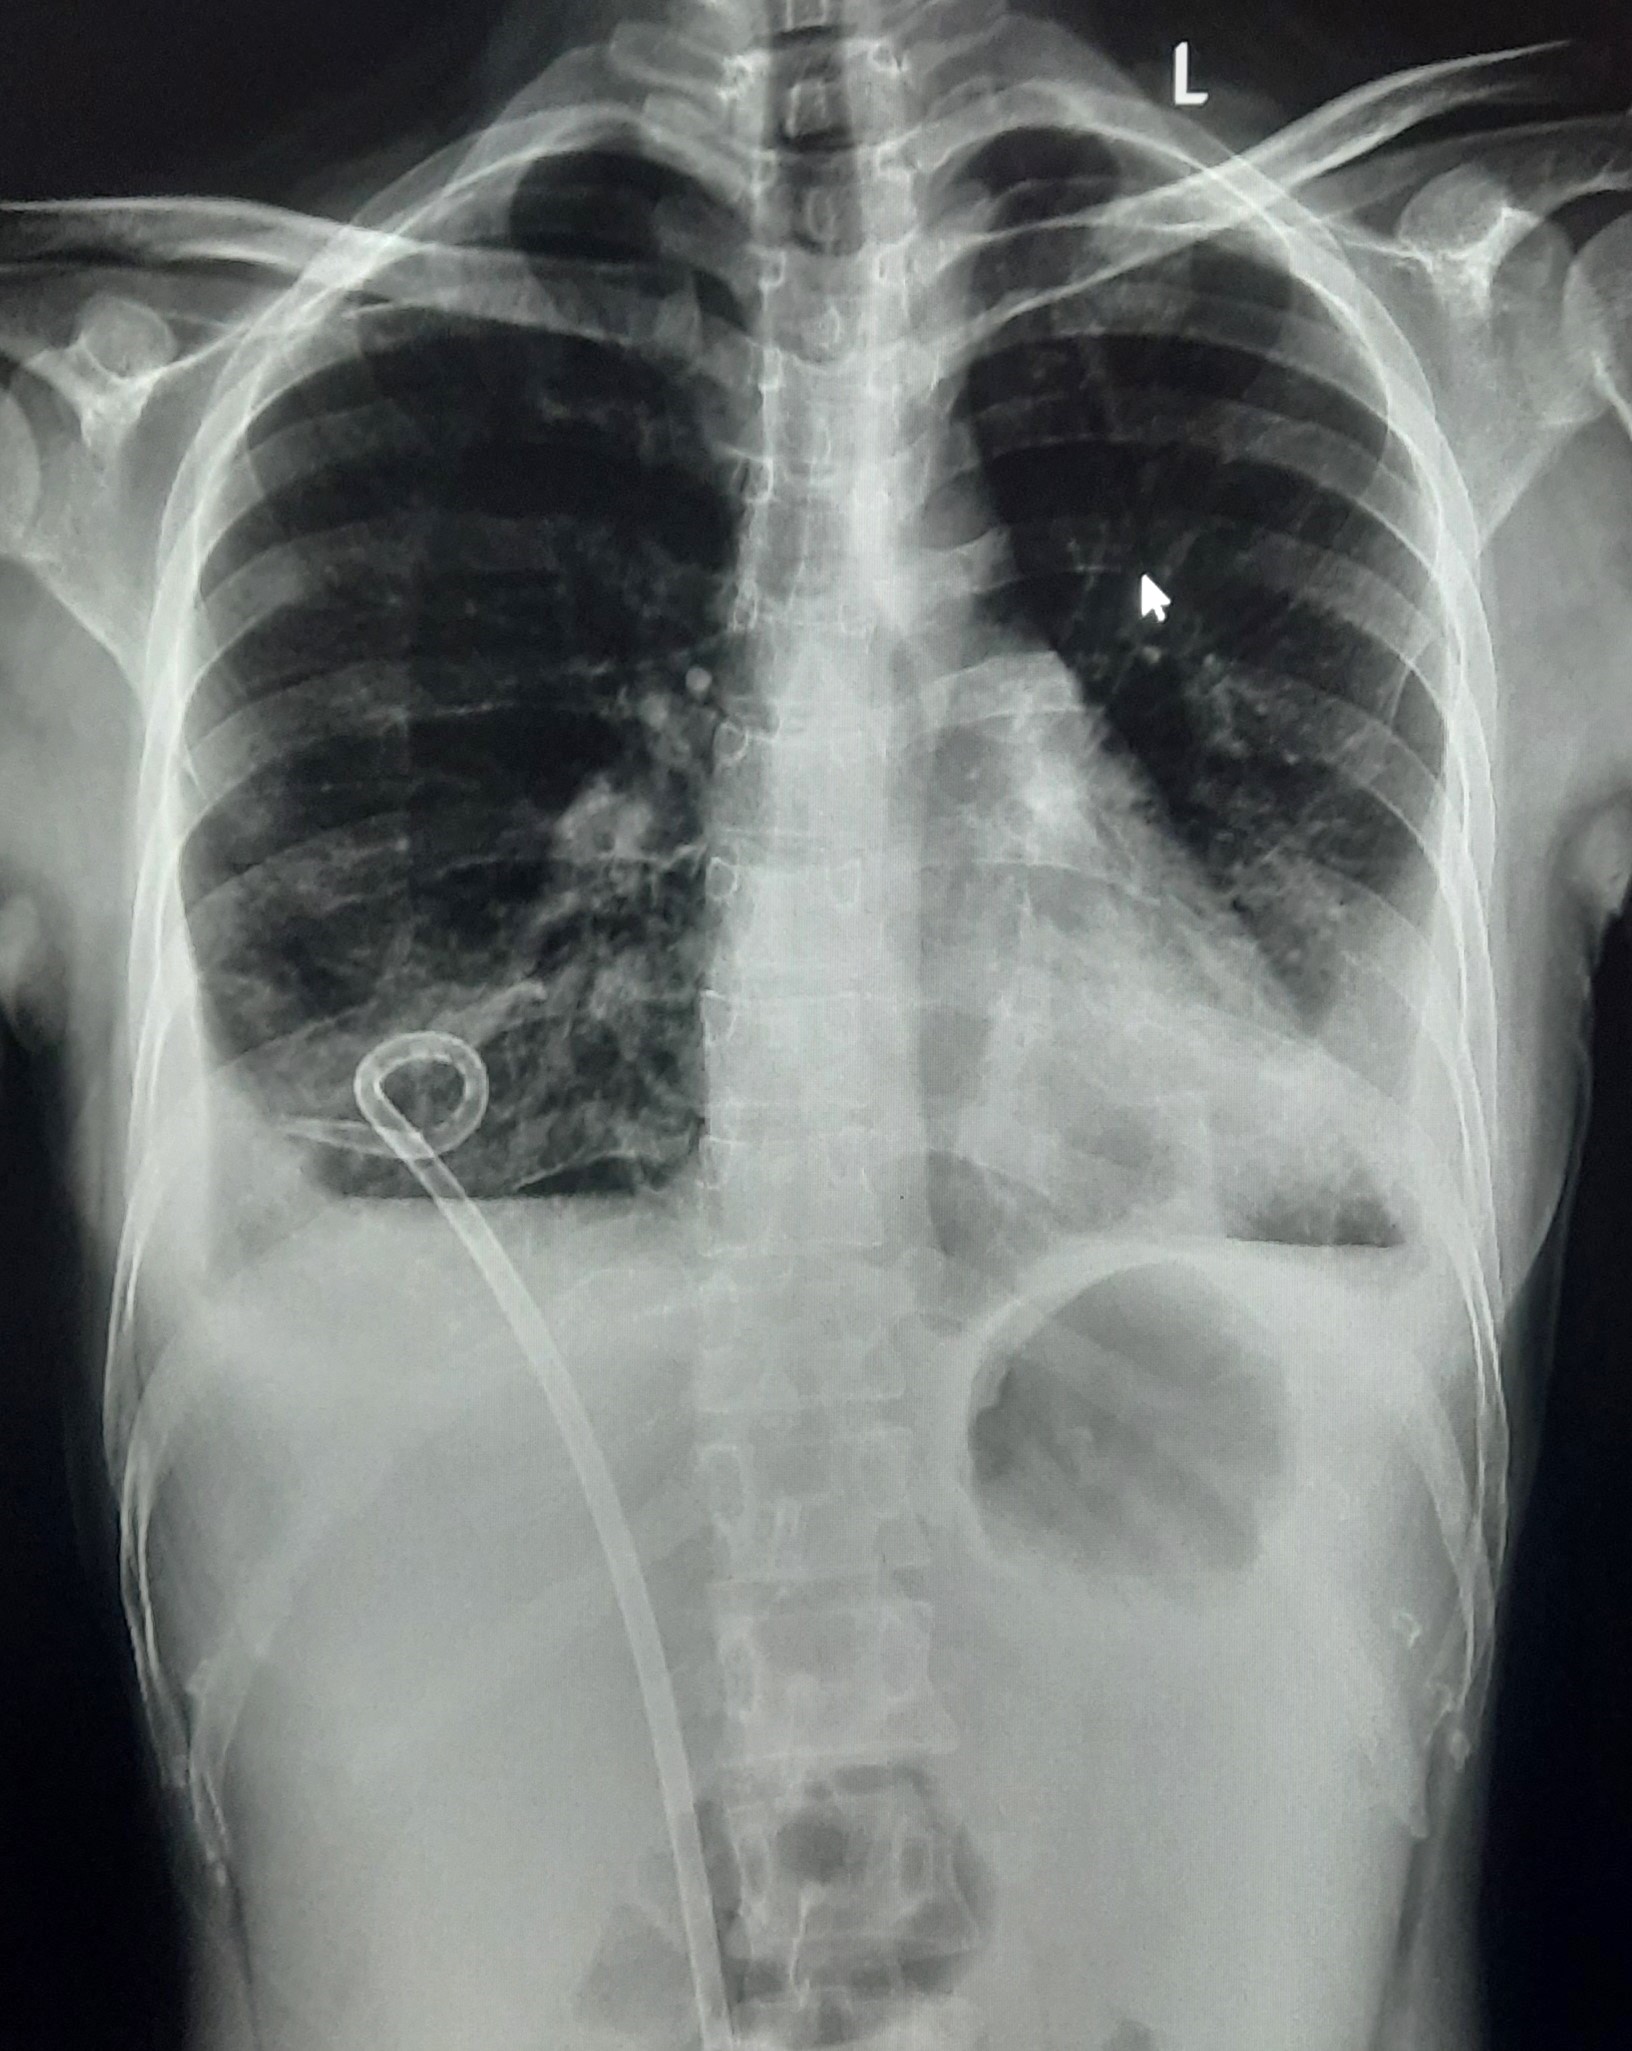

| 149 | IGGMC, Nagpur, Nagpur | P2 | 29-4323 | Samina Parveen | Consent taken on Paper | 30 Yrs. |

Provisional Diag : Bilateral Tubercular Pleural Effusion

Final Diag : Bilateral Tubercular Pleural Effusion With Right Sided Pigtail Infiltration |

TB Case (Confirmed) | Bilateral CP Angle Blunting With Bilateral Homogenous Opacity Left Zone With Pigtail Right Pleural Effusion | Abnormality visible on x-ray |